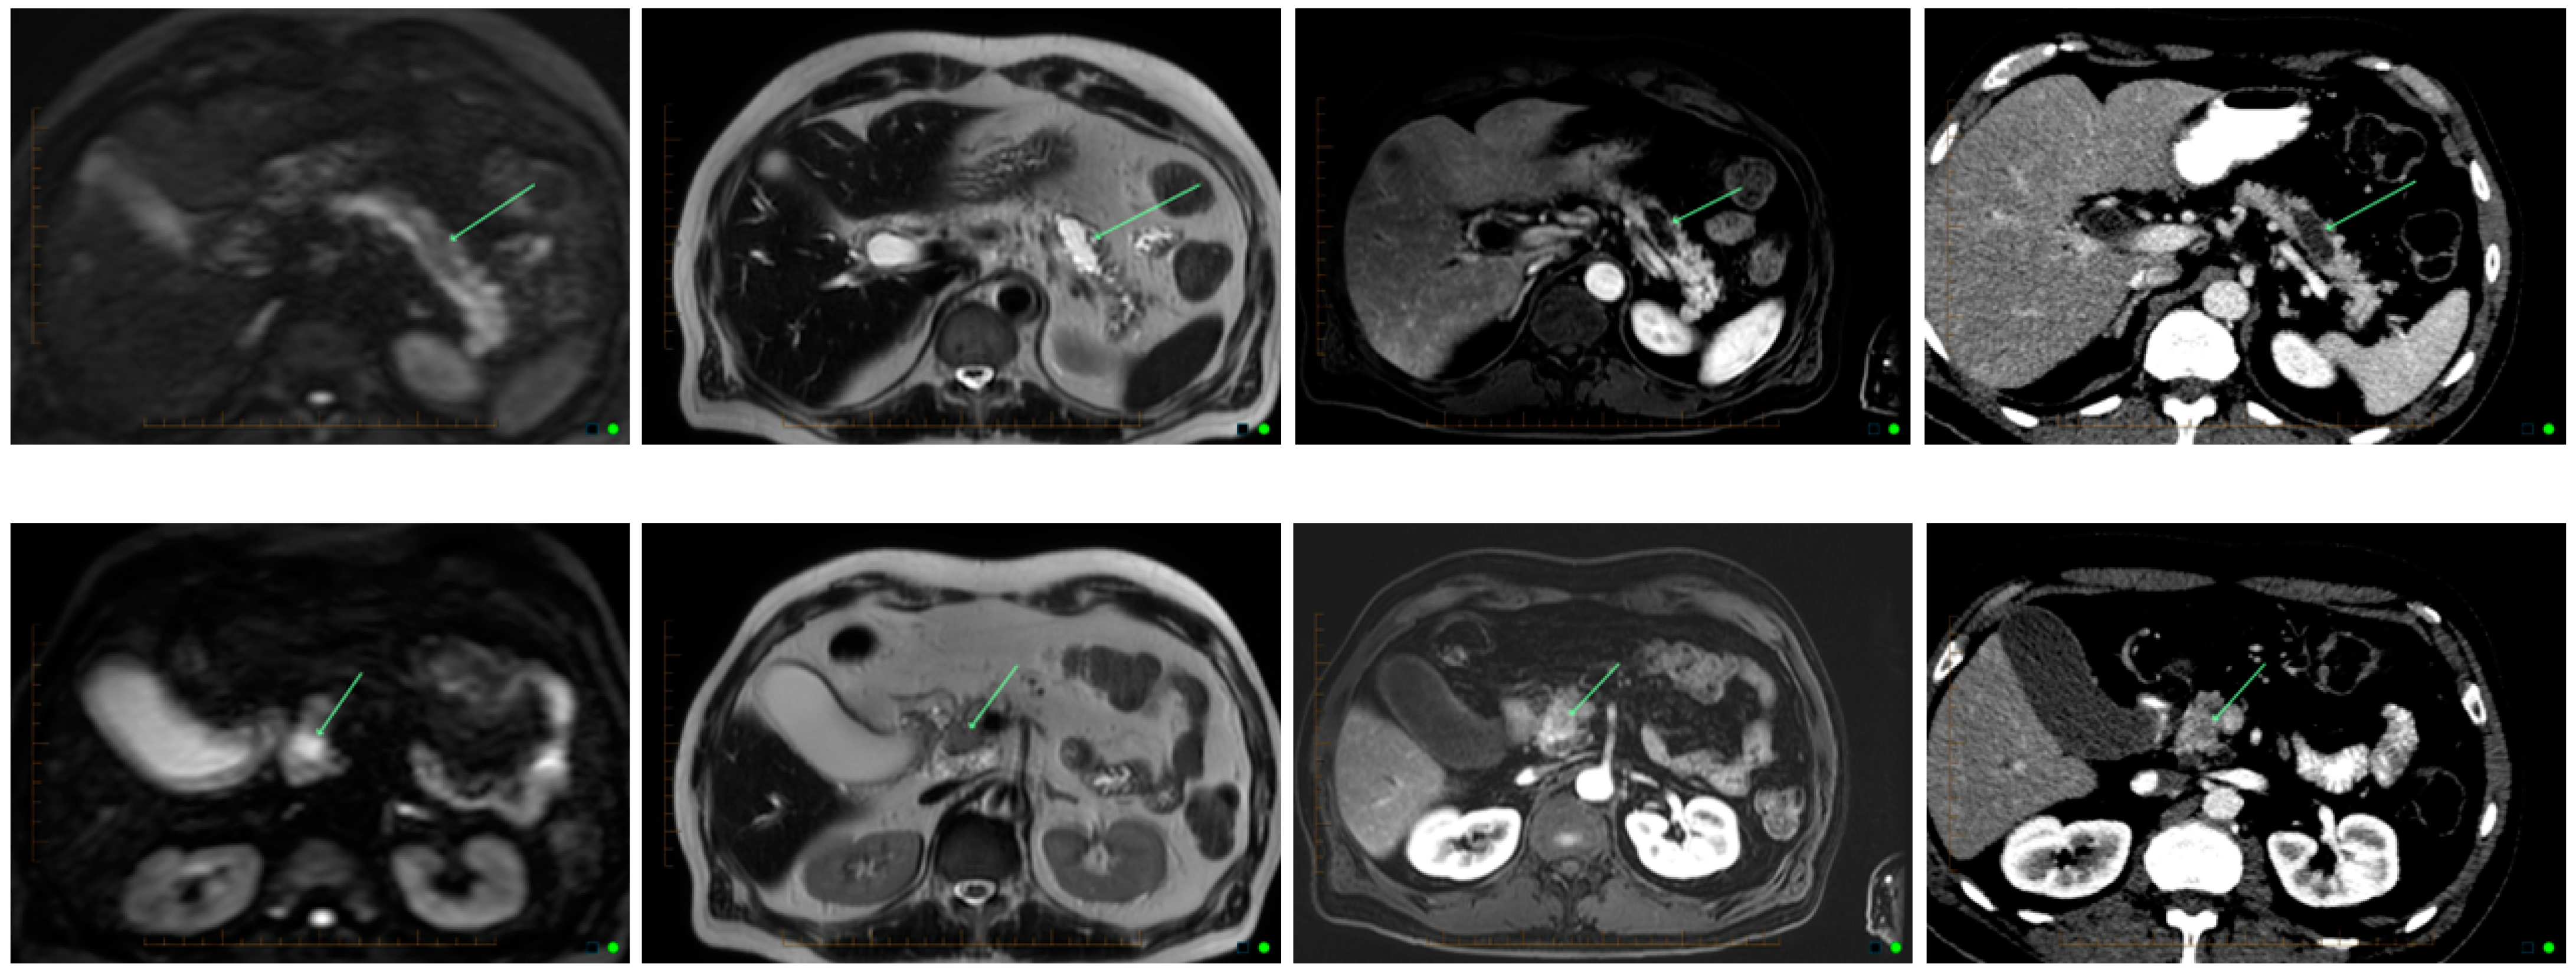

Computed tomography (CT)![]() | High sensitivity and specificity (76–92% and 67% respectively) Standardized available protocol- pancreatic protocol CT Multidetector CT Good spatial and temporal resolution Lower cost and greater availability | Radiation exposure with the risk of secondary cancer attributable to the CT procedure Performance depends on ability to administer intravenous Iodine contrast Allergies to CT contrast agents (common) Cannot detect iso-attenuating PDACs with indistinct borders and small pancreatic tumours |

Endoscopic ultrasound (EUS)![]() | High sensitivity and specificity (72% and 90% respectively) Excellent resolution for small lesions Mainly used as part of the work-up to obtain biopsy (FNA) for tissue diagnosis | Performance varies by disease T stage Invasive procedure, not practical for routine follow-up Not readily accessible imaging modality Highly dependent on technical skill of the operator Limitations for evaluating solid pancreatic lesions Procedural risks |

Magnetic resonance imaging (MRI)![]() | Highest sensitivity and specificity (93% and 89% respectively) Better soft tissue resolution No radiation exposure Better at determining metastasis Better accuracy for assessing local involvement of a pancreatic lesion | Can be difficult to obtain in patients with claustrophobia, metal devises, or allergies to gadolinium (very rare) |